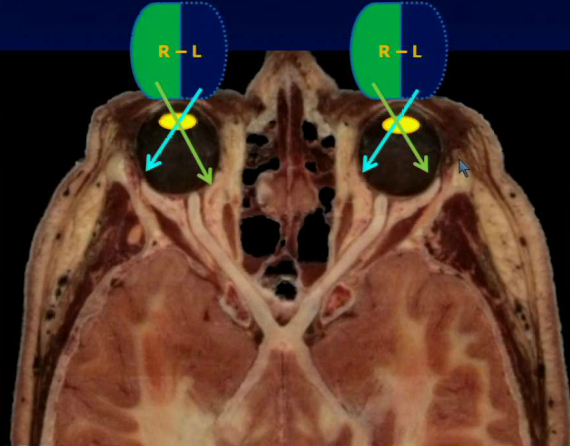

What structures are indicated below?

1) Opthalmic artery branching from carotid and going through the optic canal 2) Basilar artery

Where does the sympathetic innervation for the eye pass through?

Optic canal, it will be wound around the opthalmic artery.